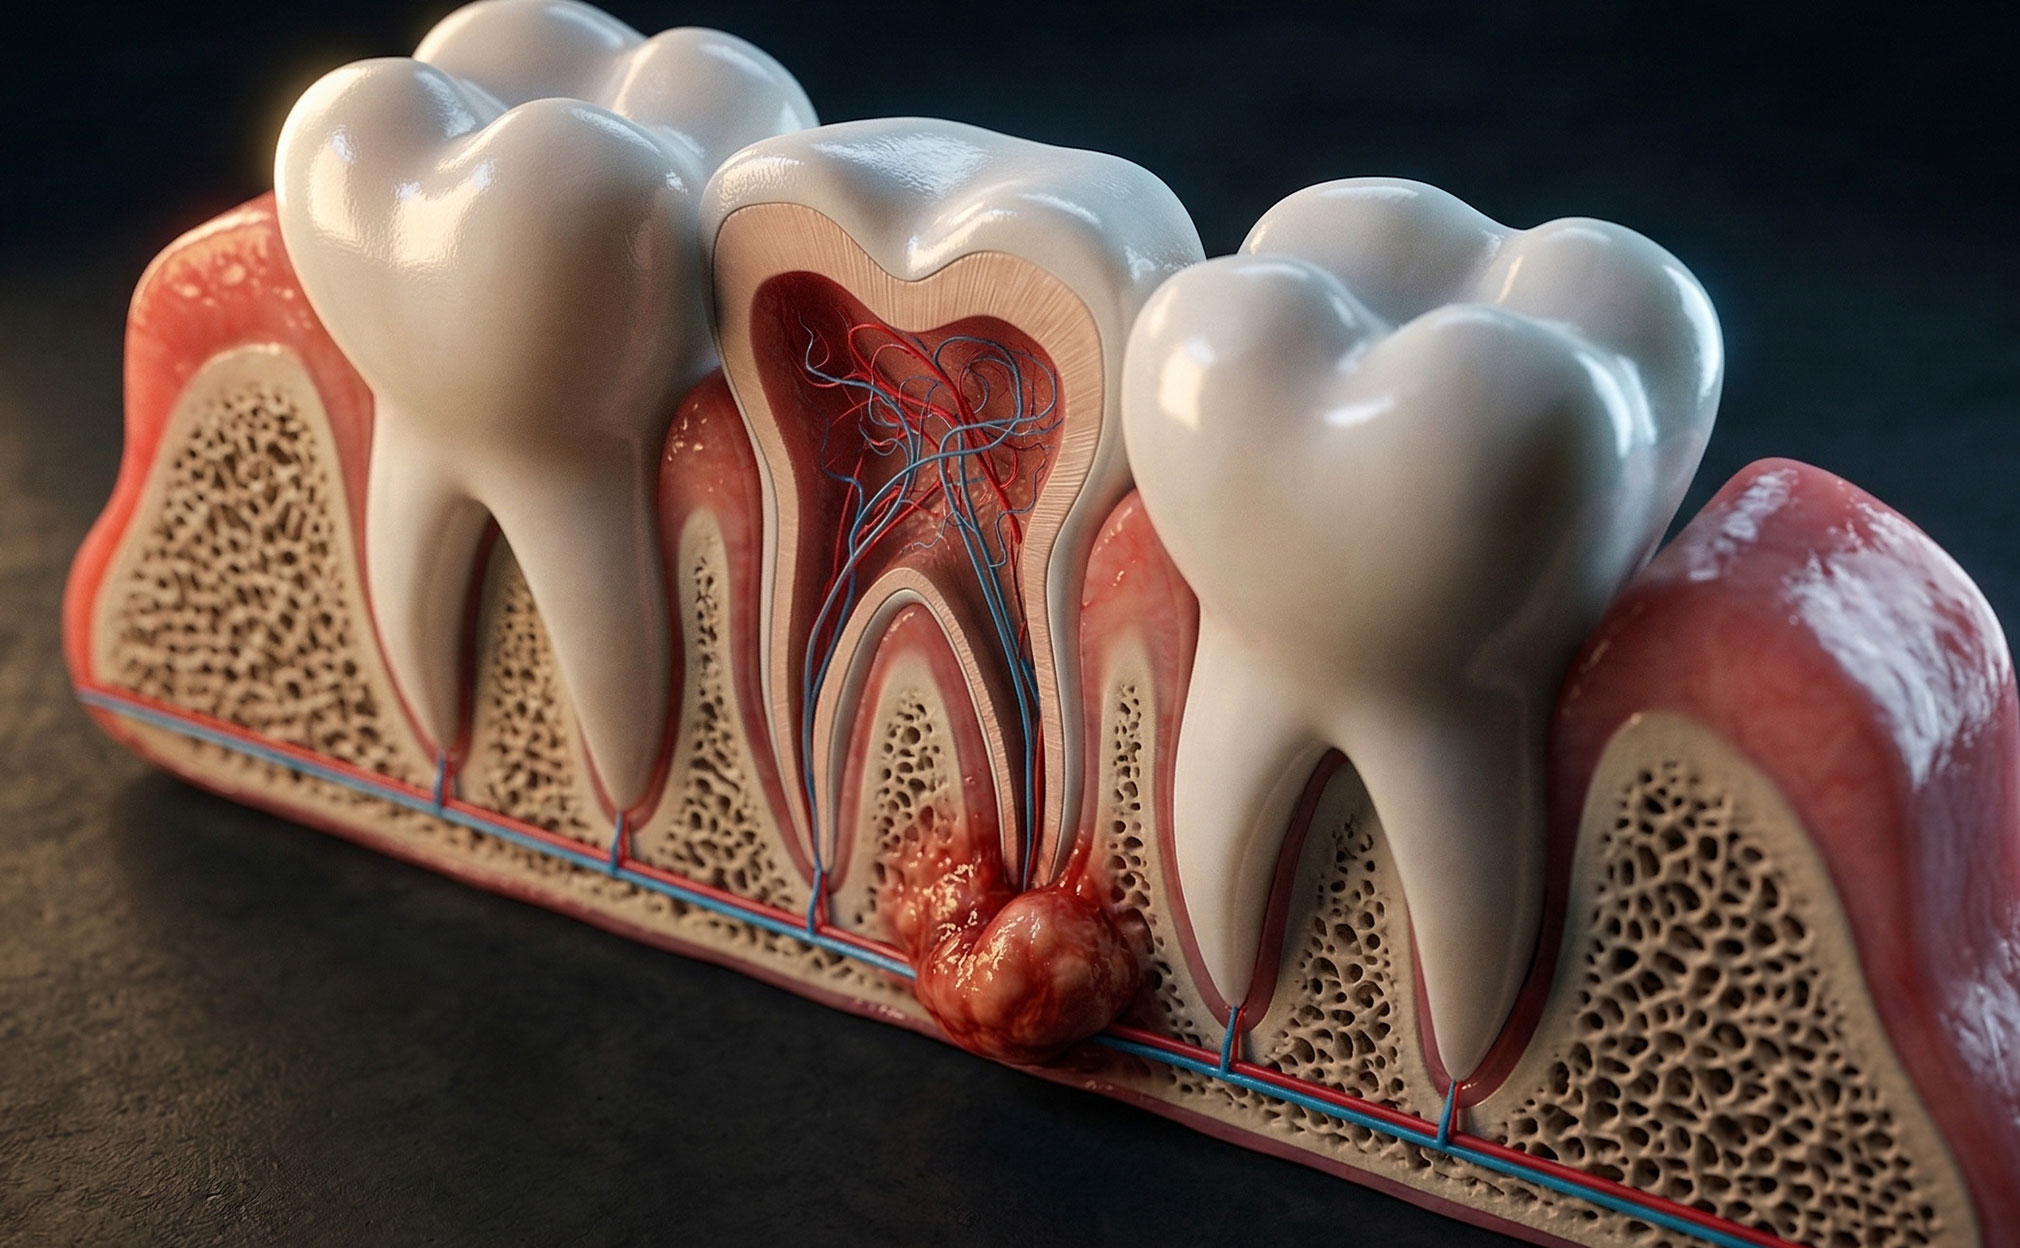

Panoramic dental X-rays display the entire jaw in a single image and are employed to determine the position of teeth, bone structure, and potential abnormalities. Dentists take panoramic X-rays for several reasons. First, they allow assessment of bone anatomy and pathology, dental development, and the extent of dental treatment. Second, they evaluate the mandible and maxillofacial region for certain lesions, cysts, and tumours not visible through intraoral films. Third, they detect gross caries, periodontal disease, or other pathology overlooked on intraoral films. Lastly, they are valuable for identifying unerupted teeth, especially wisdom teeth, and establishing their relationship to adjacent teeth (Ozmen and Basak Ayna, 2024).

Panoramic radiographs are a simple and widely used technique in dental specialties that involve synchronized rotation of an X-ray source and a stationary image receptor around the patient's head. This imaging method captures the entire maxillomandibular structure, including dental arches and related structures. It is beneficial because it involves a lower radiation dose, costs less, and images a larger area compared to intraoral radiographs. Panoramic radiography is recommended for patients with transitional or permanent dentition and can evaluate teeth, bone lesions, fractures, and foreign bodies (Couto Ramos et al., 2016).

The article explained panoramic dental X-rays, large images that capture the entire jaw’s teeth position, surrounding bone structure, sinuses, and possible tumors, cysts, or infections. A dentist may recommend one to collect comprehensive information about a patient’s dental health, especially when planning orthodontic, surgical, or wisdom tooth removal procedures. The X-ray uses a minimal dose of radiation and is noninvasive and painless.